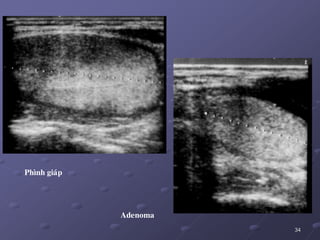

Phình giaùp

Adenoma

Böôùu laønh tuyeán giaùp:

 Böôùu tuyeán nang (follicular adenoma) +++, nguyeân nhaân do

söï taân sinh laønh tính caùc teá baøo nang tuyeán giaùp, coù voû bao xô

quanh nhaân vaø khoâng bao giôø trôû thaønh ung thu giaùp. Tuy nhieân

khoù CÑPB toån thöông laønh tính naøy vôùi ung thö giaùp daïng nang.

 SA: nhaân echo daày hay ñoàng echo vôùi chuû moâ giaùp.

Khoâng theå phaân bieät ñöôïc caùc loaïi toåân thöông daïng nang baèng

SA hay teá baøo hoïc  caàn phaåu thuaät.